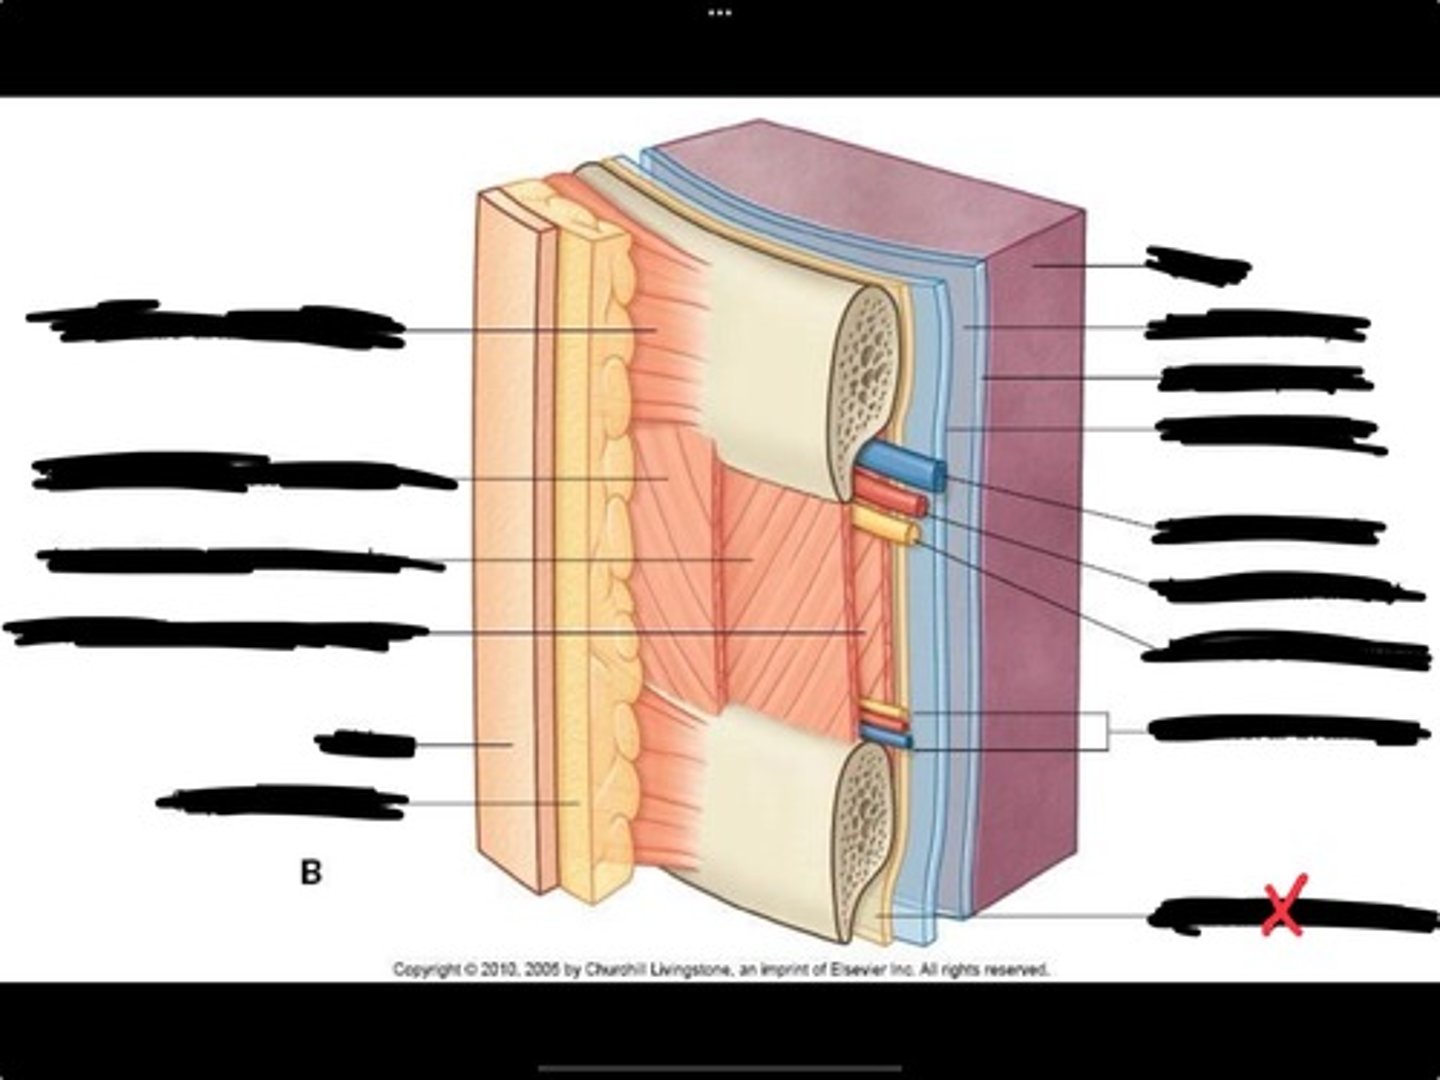

Innermost intercostal muscle

Skin

Internal intercostal muscle

External intercostal muscle

Serratus anterior muscle

Lung

Pleural cavity

Visceral pleura

Parietal cavity

Intercostal vein

Intercostal artery

Collateral branches

Intercostal nerve

Endothoracic fascia

Diaphragm